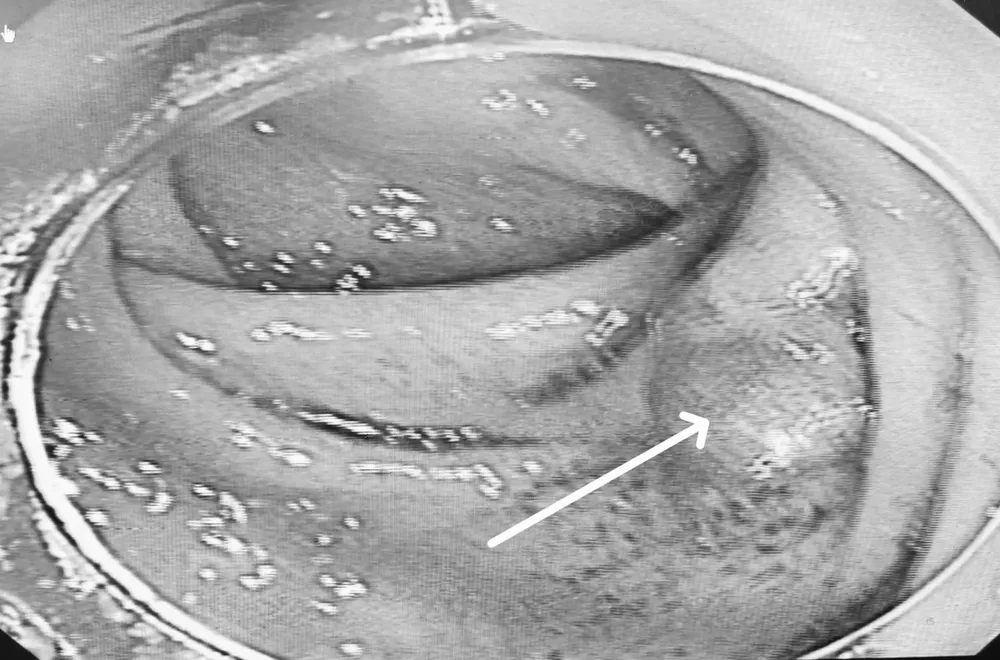

Sau 2 giờ mổ, khối u dạng sùi và nhiều polyp đã được lấy bỏ, gửi giải phẫu bệnh để xác định nguy cơ ác tính.

Khối u sùi vùng manh tràng. Ảnh: BVCC